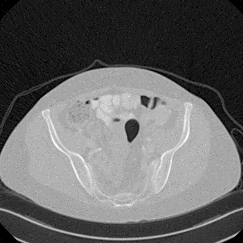

In this work, we present Eformer - Edge enhancement based transformer, a novel architecture that builds an encoder-decoder network using transformer blocks for medical image denoising. Non-overlapping window-based self-attention is used in the transformer block that reduces computational requirements. This work further incorporates learnable Sobel-Feldman operators to enhance edges in the image and propose an effective way to concatenate them in the intermediate layers of our architecture. The experimental analysis is conducted by comparing deterministic learning and residual learning for the task of medical image denoising. To defend the effectiveness of our approach, our model is evaluated on the AAPM-Mayo Clinic Low-Dose CT Grand Challenge Dataset and achieves state-of-the-art performance, $i.e.$, 43.487 PSNR, 0.0067 RMSE, and 0.9861 SSIM. We believe that our work will encourage more research in transformer-based architectures for medical image denoising using residual learning.